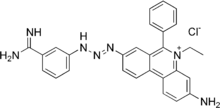

Isometamidium chloride is a triazene trypanocidal agent used in veterinary medicine.[1][2]

It consists of a single ethidium bromide like subunit linked to a fragment of the diminazene molecule.